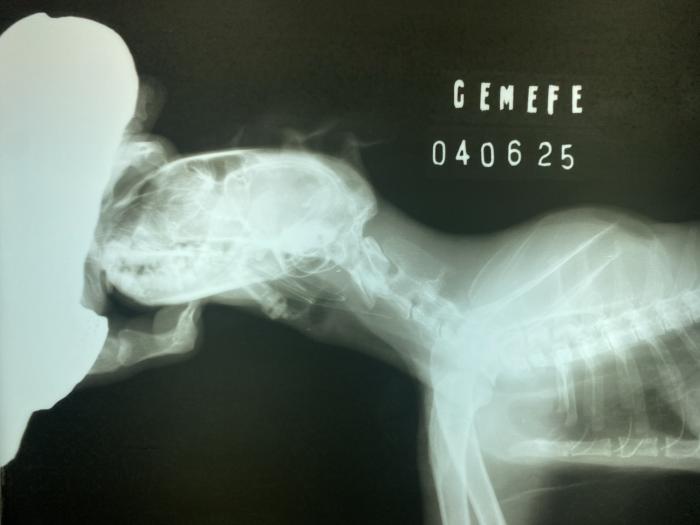

Hay una demora del tercer procedimiento, indicado inicialmente cada 2-4 días, la cual desencadena una complicación no esperada. Originando un aparente cierre completo de la estenosis cervical craneal, el paciente no tolera líquidos ni comidas. La tutora acude a consulta, informando que aparentemente estaría broncoaspirando. Realizamos estudios de imágenes radiográficas, donde se descarta esta posible complicación, pero determinamos el cierre de la estenosis esofágica cervical craneal, con la imposibilidad de colocación de sonda nasoesofágica (sonda de 3.5 F). Luego de varios intentos infructuosos, se comunica este impedimento, con el cual determinamos la estenosis completa, o de mayor gravedad impidiendo el paso de todo tipo de sonda (Figura 6A-C).

Figura 6. (A) Proyección laterolateral de tórax donde descartamos una posible broncoaspiración. (B) Imagen radiográfica obtenida durante el intento de colocación de una nueva sonda de alimentación esofágica. (C) Se puede evidenciar como la punta de la sonda ingresa por el esfínter esofágico anterior. Dilatación del segmento inicial del esófago cervical y caudal a la misma, disminución de la luz esofágica compatible con una estenosis severa.